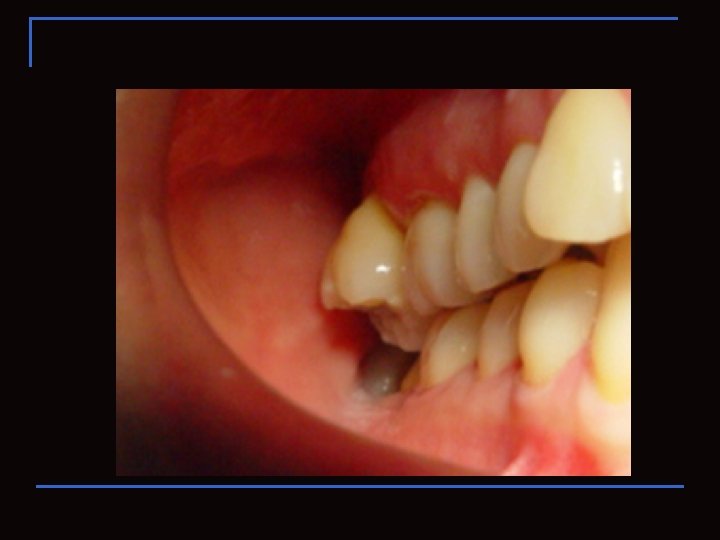

Área retromolar